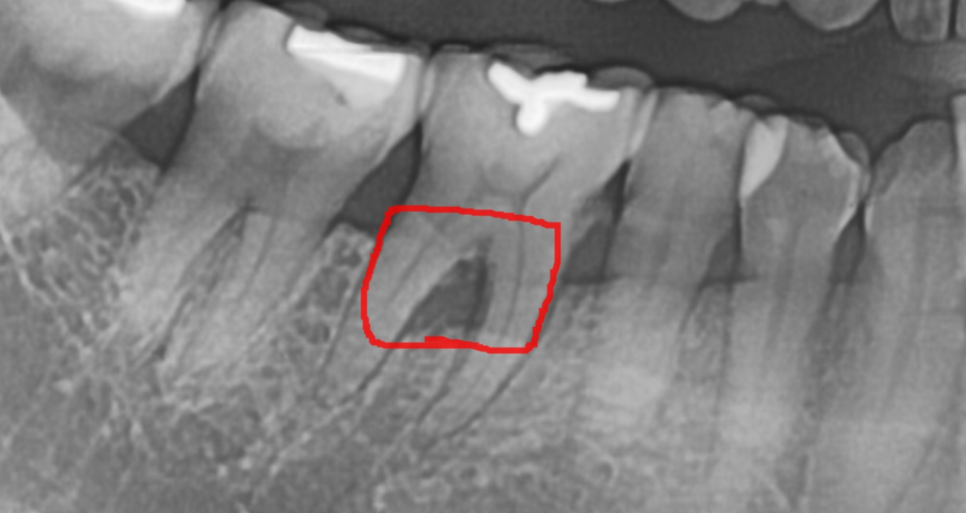

치아가 보내는 속마음

조금씩 녹을 때는 겉으로 증상이 나타나지 않기 때문에

환자분은 모르시는 경우가 많아요.

치과에 방문하여 x-ray를 찍어보기 전까지는 말이죠.

이러한 이유로 x-ray는 필수로 찍어보시는게 좋습니다.

250326 잇몸뼈가 녹은 부위는 까맣게 관찰됩니다.